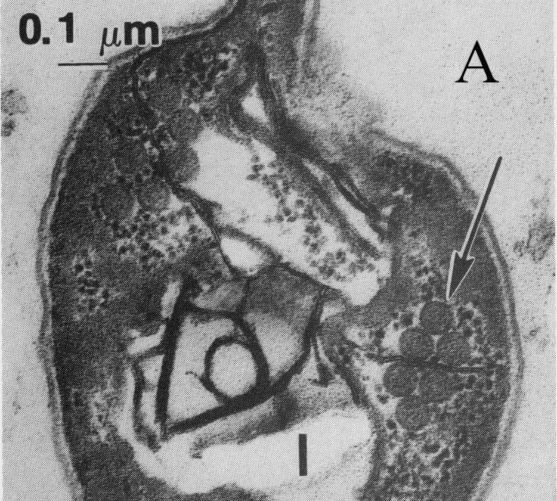

图1 比氏肠微孢子虫孢子的透射电子显微图(A)[2]和孢子染色图(×1800)(B)[2]

比氏肠微孢子虫的孢子大小约为0.9×1.5 μm,卵圆形,无鞭毛,染色时有特殊的外观。孢子壁染成亮粉红色;有些孢子透明,另一些则呈明显的粉红色带状条纹,呈对角线或赤道线环绕孢子。粪便标本中的大多数背景碎片复染为淡绿色[2]。